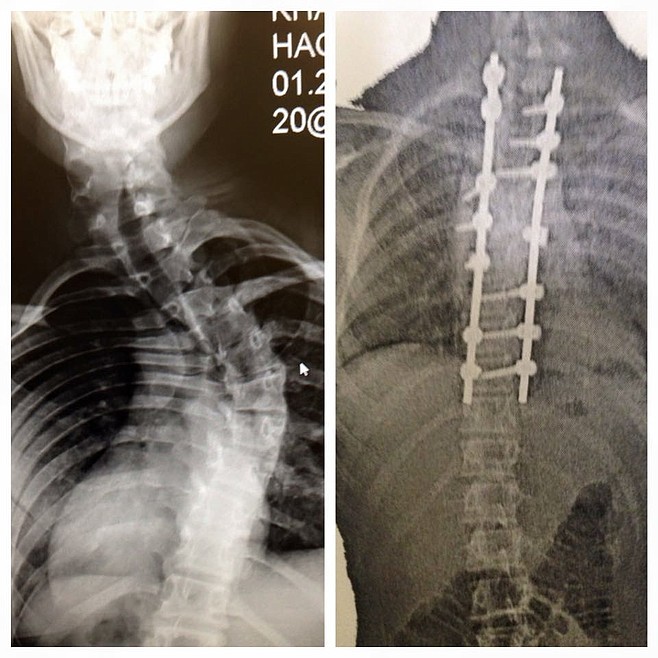

X-rays of Khalyn Hageness's spine before and after the surgery that fused the vertebrae in her upper back with steel rods. (Photo courtesy Kindra Hageness)

The star pitcher of Libby High School’s Softball team this past season was born with idiopathic scoliosis, causing her spine to curve, and potentially fatal.

The family received a recommendation for a specialist at Twin City Spine in Minneapolis, Kindra said. In her 8th grade year, Khalyn’s spine already had over 60 degrees of curvature.

After the surgery to fuse the vertebrae in her upper spine, Khalyn still has things to deal with, from sore muscles to the rod that sticks up near the back of her neck.